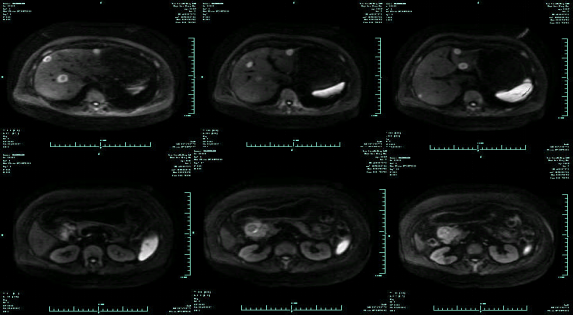

MR-H1

影像学检查结果评估:cPD。